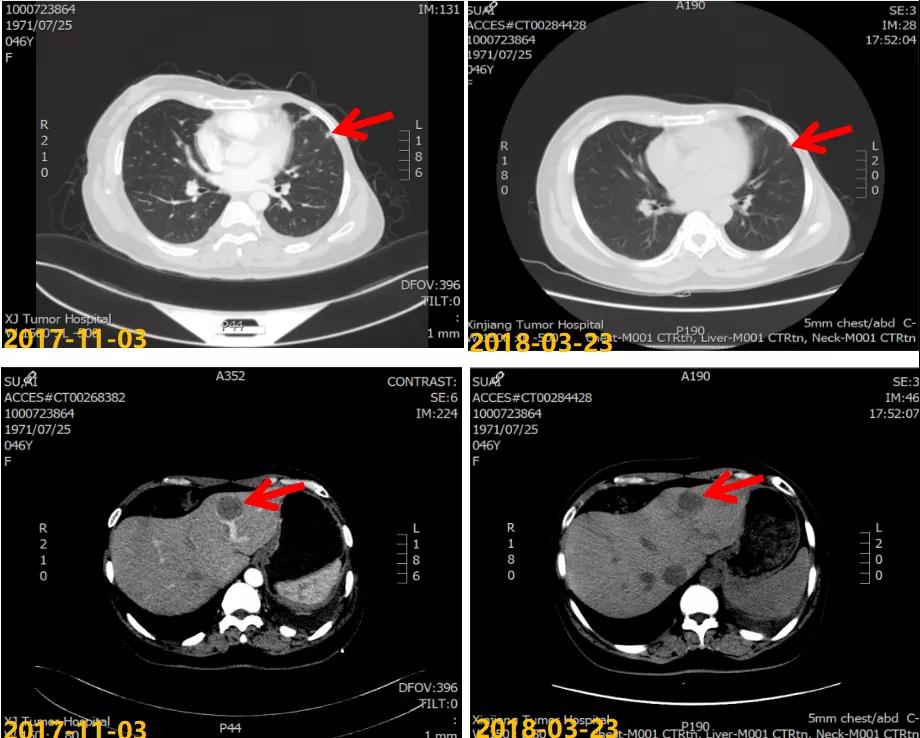

第一次病情进展: 2017-10-22患者因“气喘气憋、呼吸困难20天”就诊我院,胸水超声提示左侧大量胸腔积液,行胸水穿刺引流,查见癌细胞。2017-11-03 CT:两肺多发结节,考虑转移瘤;左侧胸膜斑块状增厚,提示胸膜转移;肝脏多发转移瘤。进一步行肝脏肿块穿刺活检,病理:ER(2+,90%),PR(3+,80%),HER2(2+),Ki-67(+,40%),FISH检测:未观测到基因扩增。

2017-11至2018-03:TX方案6周期(多西他赛120mg d1+卡培他滨1500mg po bid d1-14),化疗期间继续戈舍瑞林3.6mg ih q4w。疗效评估:前四周期略缩小但未达PR,后两周期SD,呼吸道症状明显改善。2018-04行戈舍瑞林3.6mg ih q4w联合氟维司群 500mg im q4w内分泌维持治疗,同时经MDT多学科讨论后行肝脏射频消融术。一线治疗获得36个月PFS。